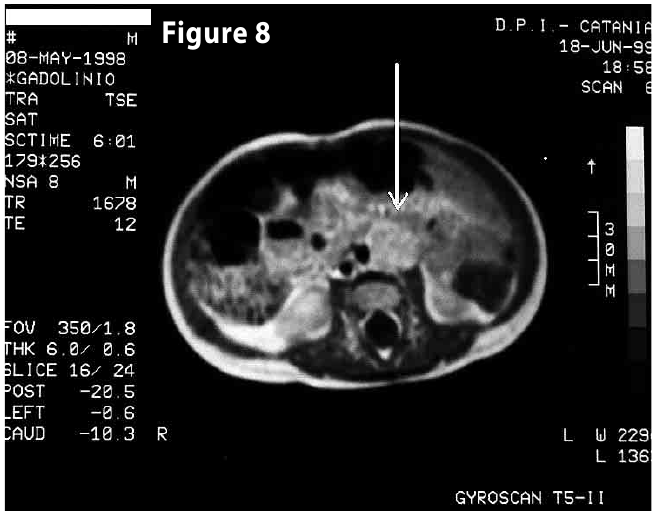

Figure8